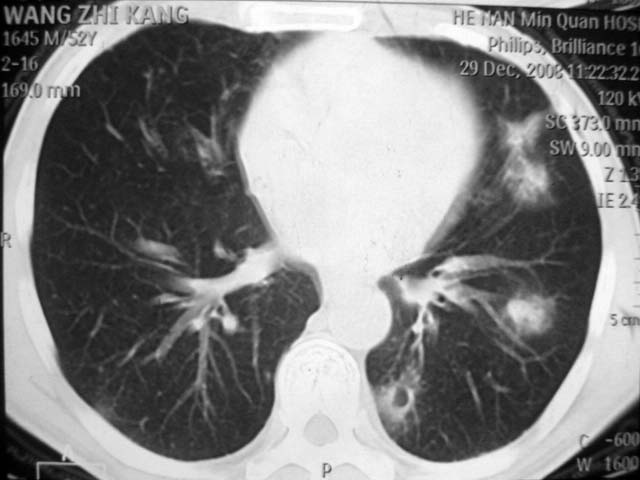

男,52岁,发热2月,糖尿病史。

抗结核治疗irpz方案,血糖未治疗,空腹15.9左右。症状无好转,左胸痛。

2、双肺见多发片状及结节状高密度影,大多数病灶中心均见“空泡征”。

3、纵隔内淋巴结肿大。

结果:两肺继发性肺结核并曲霉菌感染。